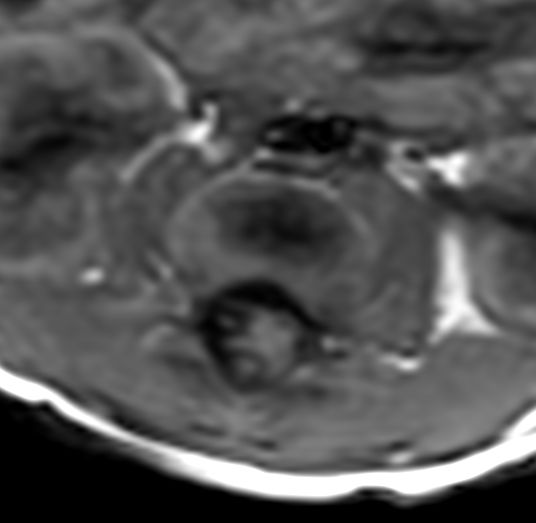

Pediatric Total Spine with spina bifida

Neonatal patient, 5 days old, with spina bifida